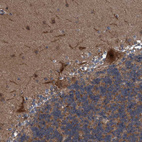

Immunohistochemical staining of human cerebellum shows strong cytoplasmic and membranous positivity in Purkinje cells.